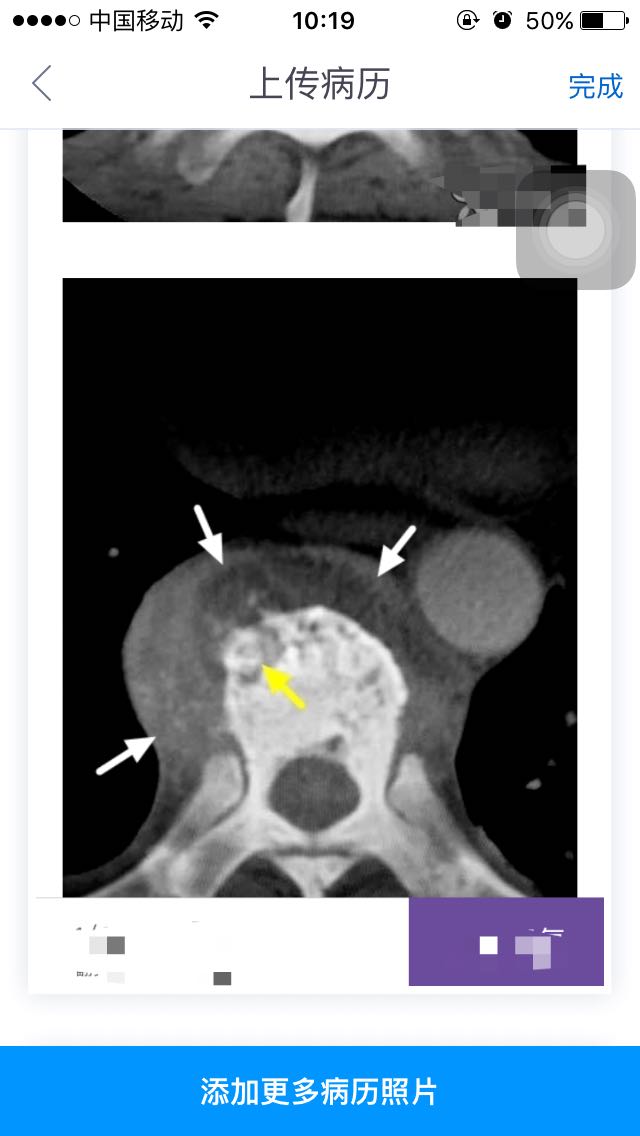

查体下肢已无感觉运动。行PET-CT结果考虑结核病灶并未见肿瘤性质病损,考虑胸8、9椎体结核,胸7、11、腰2考虑良性病变。CT、MRI均考虑转移瘤。红细胞沉降率34mm/h,肿瘤指标为糖类抗原12-5 34.43U/l(小于35)。体重消瘦约7kg,半年。无明显乏力、纳差、午后低热。 影像表现:多发胸椎骨质破坏,其内可见死骨(黄箭)。邻近椎间隙变窄,椎旁软组织增厚,CT示内部有液体密度区,MRIT1呈略低信号,T2成高信号。符合冷脓肿(白箭)。